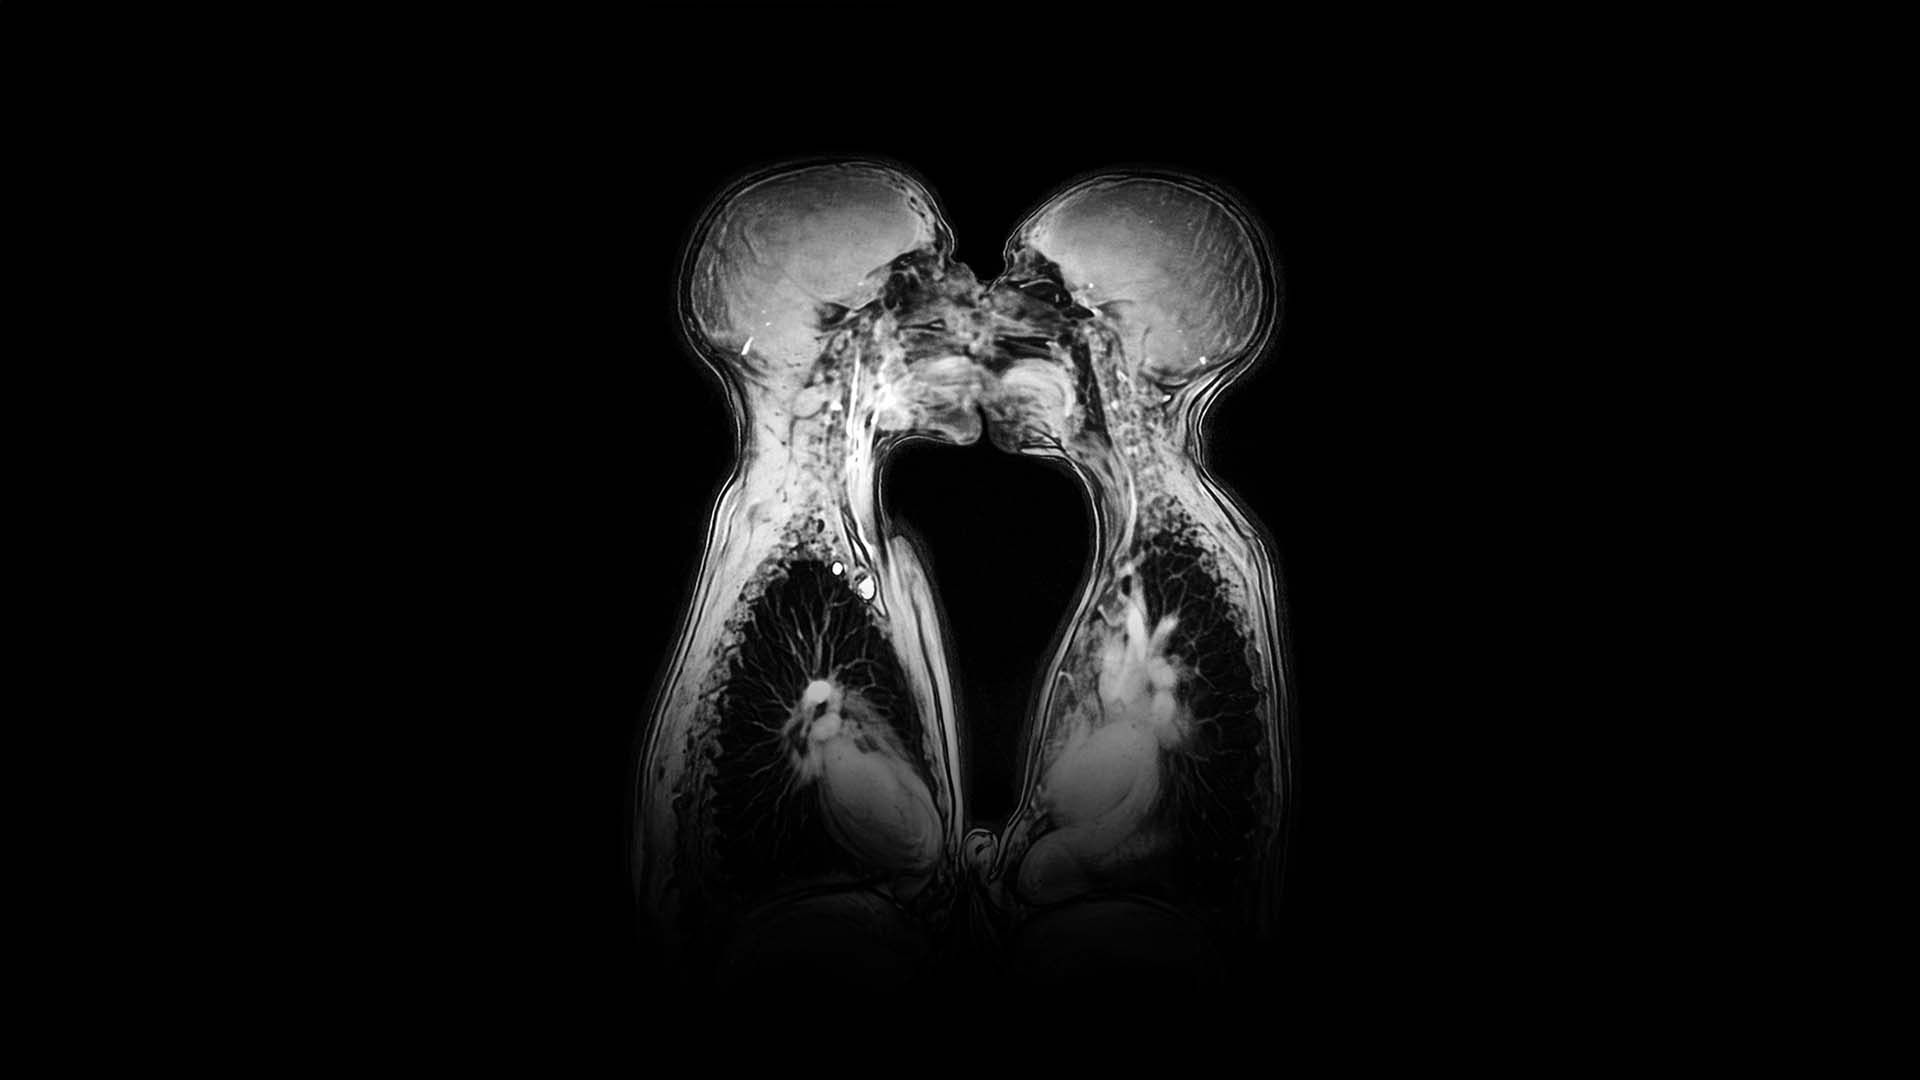

Hollandalı bilim insanı Menko van Andel öncülüğünde yürütülen bu çalışma, elde edilen yüksek çözünürlüklü görüntülerle tıp literatüründeki pek çok yerleşik yanlışı düzeltti. Teknoloji sayesinde ilk kez erkek ve kadın anatomisinin birleşme anındaki etkileşimi ve organların hareketleri canlı olarak izlendi. Sonuçlar oldukça şaşırtıcıydı; görüntüler, penisin birleşme sırasında sanılanın aksine düz bir formda kalmadığını, "bumerang" benzeri bir kıvrım aldığını ve organın büyük bir kısmının aslında vücut içinde saklı kaldığını ortaya koydu. Ayrıca, kadın anatomisinde uterusun ve vajinal duvarların uyarılma esnasında nasıl yer değiştirdiği ve şekil aldığı detaylıca haritalanarak tıbbi kitaplardaki eksik bilgiler güncellendi.